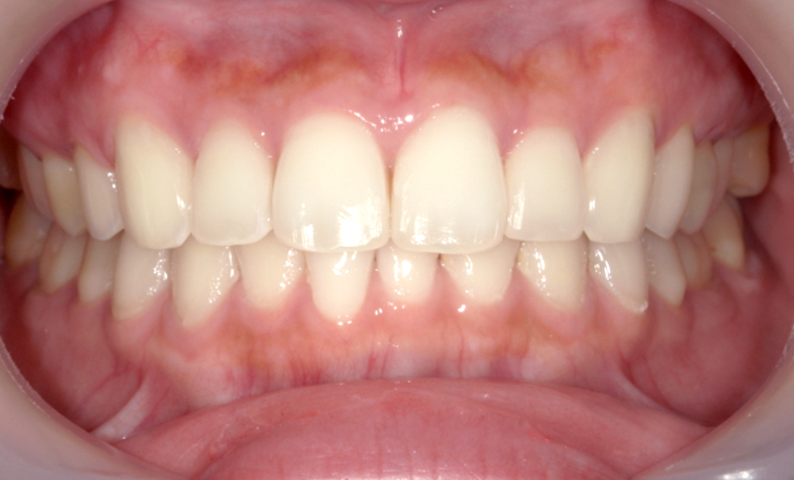

症例_001 前歯「捻転歯」症例

治療期間:6ヶ月金額:48万円+税20代女性少しのねじれ捻転歯下の八重歯

| Before | After |